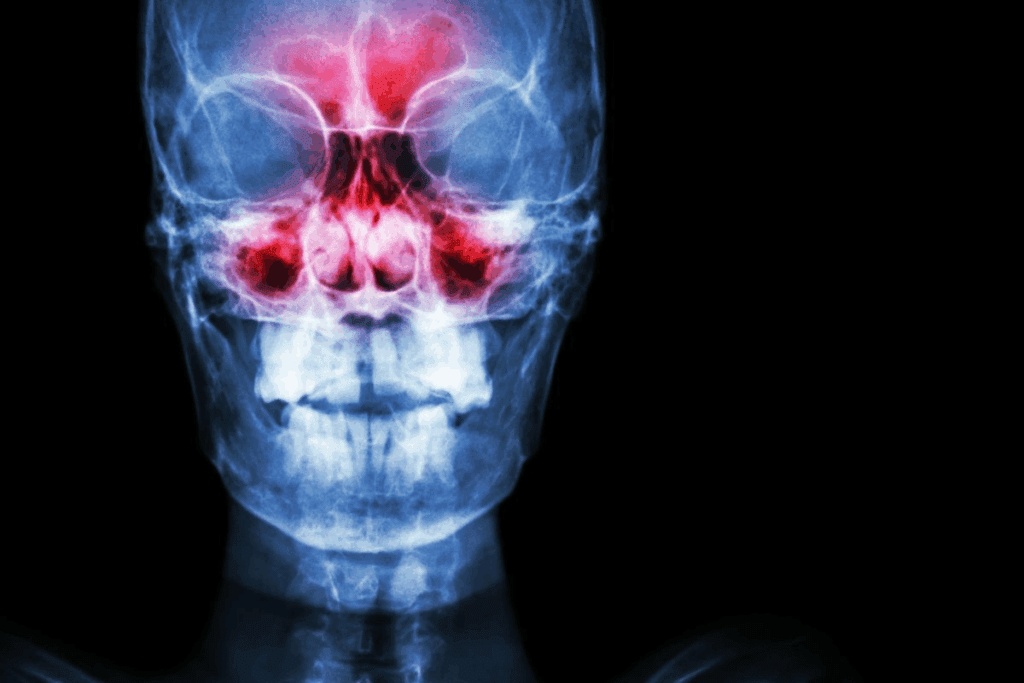

The Anatomy and Function of Sinuses

The sinuses are air-filled spaces in the nose’s passages. They make mucus to humidify the air and filter out dust and bacteria. There are four pairs of sinuses: frontal, maxillary, ethmoid, and sphenoid. The mucus drains into the nasal cavity through small channels.

Specific Sinuses Most Likely to Cause Neck Pain

The sphenoid and ethmoid sinuses play a big role in neck pain caused by sinuses. These sinuses are deep in the skull, close to the neck. When they get inflamed or infected, they can send pain to the neck.

Sphenoid Sinuses and Their Connection to the Neck

The sphenoid sinuses are in the sphenoid bone, at the skull’s base. They are near the neck and nerves. This makes them a big reason for neck pain when they get sick or inflamed.